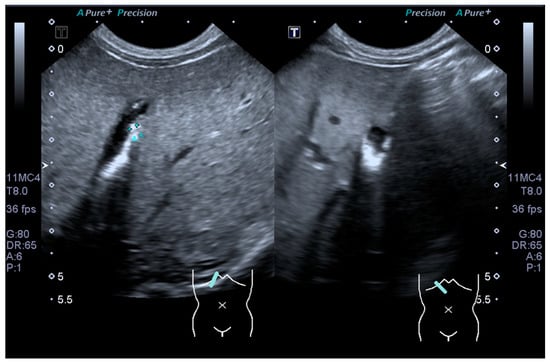

An ultrasound kidney-ureter-bladder (KUB) revealed bilateral hydronephrosis, right renal urinary tract dilatation (UTD) of moderate risk and left renal UTD of low risk. There were incidental findings of multiple echogenic foci within the gallbladder, with posterior shadowing suggestive of cholelithiasis (Figure 1). However, repeated ultrasound hepatobiliary by paediatric radiologist reported as gallbladder sludge.

Figure 1. Ultrasound picture showing multiple echogenic foci within the gallbladder with posterior shadowing suggestive of sludge.